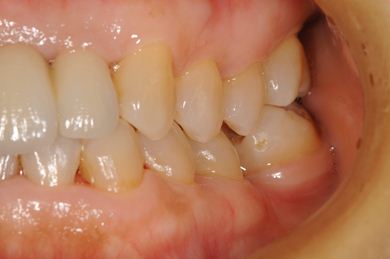

| 性別/年齢 | 女性 / 52歳 | ||||||||||||||||||||||||||||||||

| 主訴 | 歯周病で歯の位置がずれてしまった。 | ||||||||||||||||||||||||||||||||

| 治療内容 | インプラント2本(抜歯即日スピードインプラント)、メタルボンドセラミッククラウン4本 | ||||||||||||||||||||||||||||||||